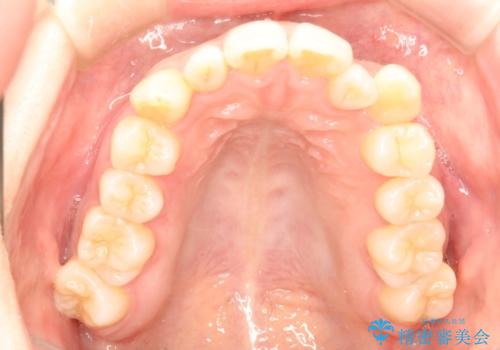

インビザラインで八重歯の矯正

- 八重歯を治したいとのことで、来院されました。

インビザラインにて、上顎の歯と歯の間をわずかに削り、並べる計画としました。